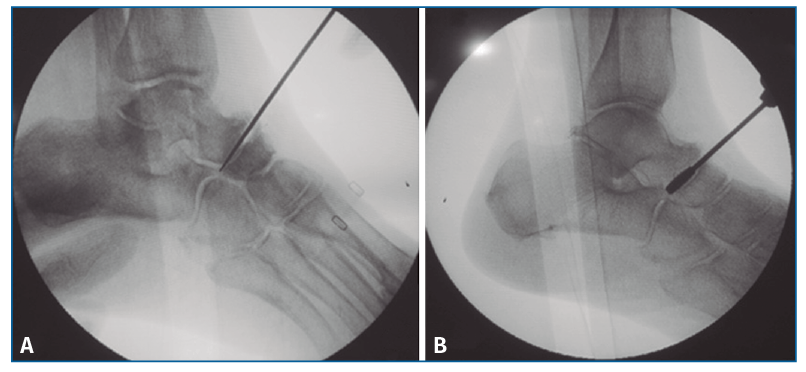

En primer lugar, se aborda la articulación TN como indican Carranza et al.(29); para ello, se marca en la piel el paquete neurovascular dorsal, se chequea la articulación por control fluoroscópico con una aguja intramuscular colocada entre el tendón tibial anterior (TA) y el extensor largo (EHL). Se realiza una incisión solo cutánea de 1 cm sobre la línea articular como el portal artroscópico dorsomedial descrito por Lui(24). Para evitar lesionar la arteria pedia o el nervio peroneal profundo, se realiza disección roma y penetración de la articulación astrágalo-escafoidea lo más cerca posible del TA. Finalmente, se cruenta la articulación bajo control fluoroscópico hasta tejido subcondral con escoplos y brocas motorizadas (Figura 1).

Figura 1. Cruentación de la articulación astrágalo-escafoidea, bajo control fluoroscópico, hasta tejido subcondral, con escoplos (A) y brocas motorizadas (B).